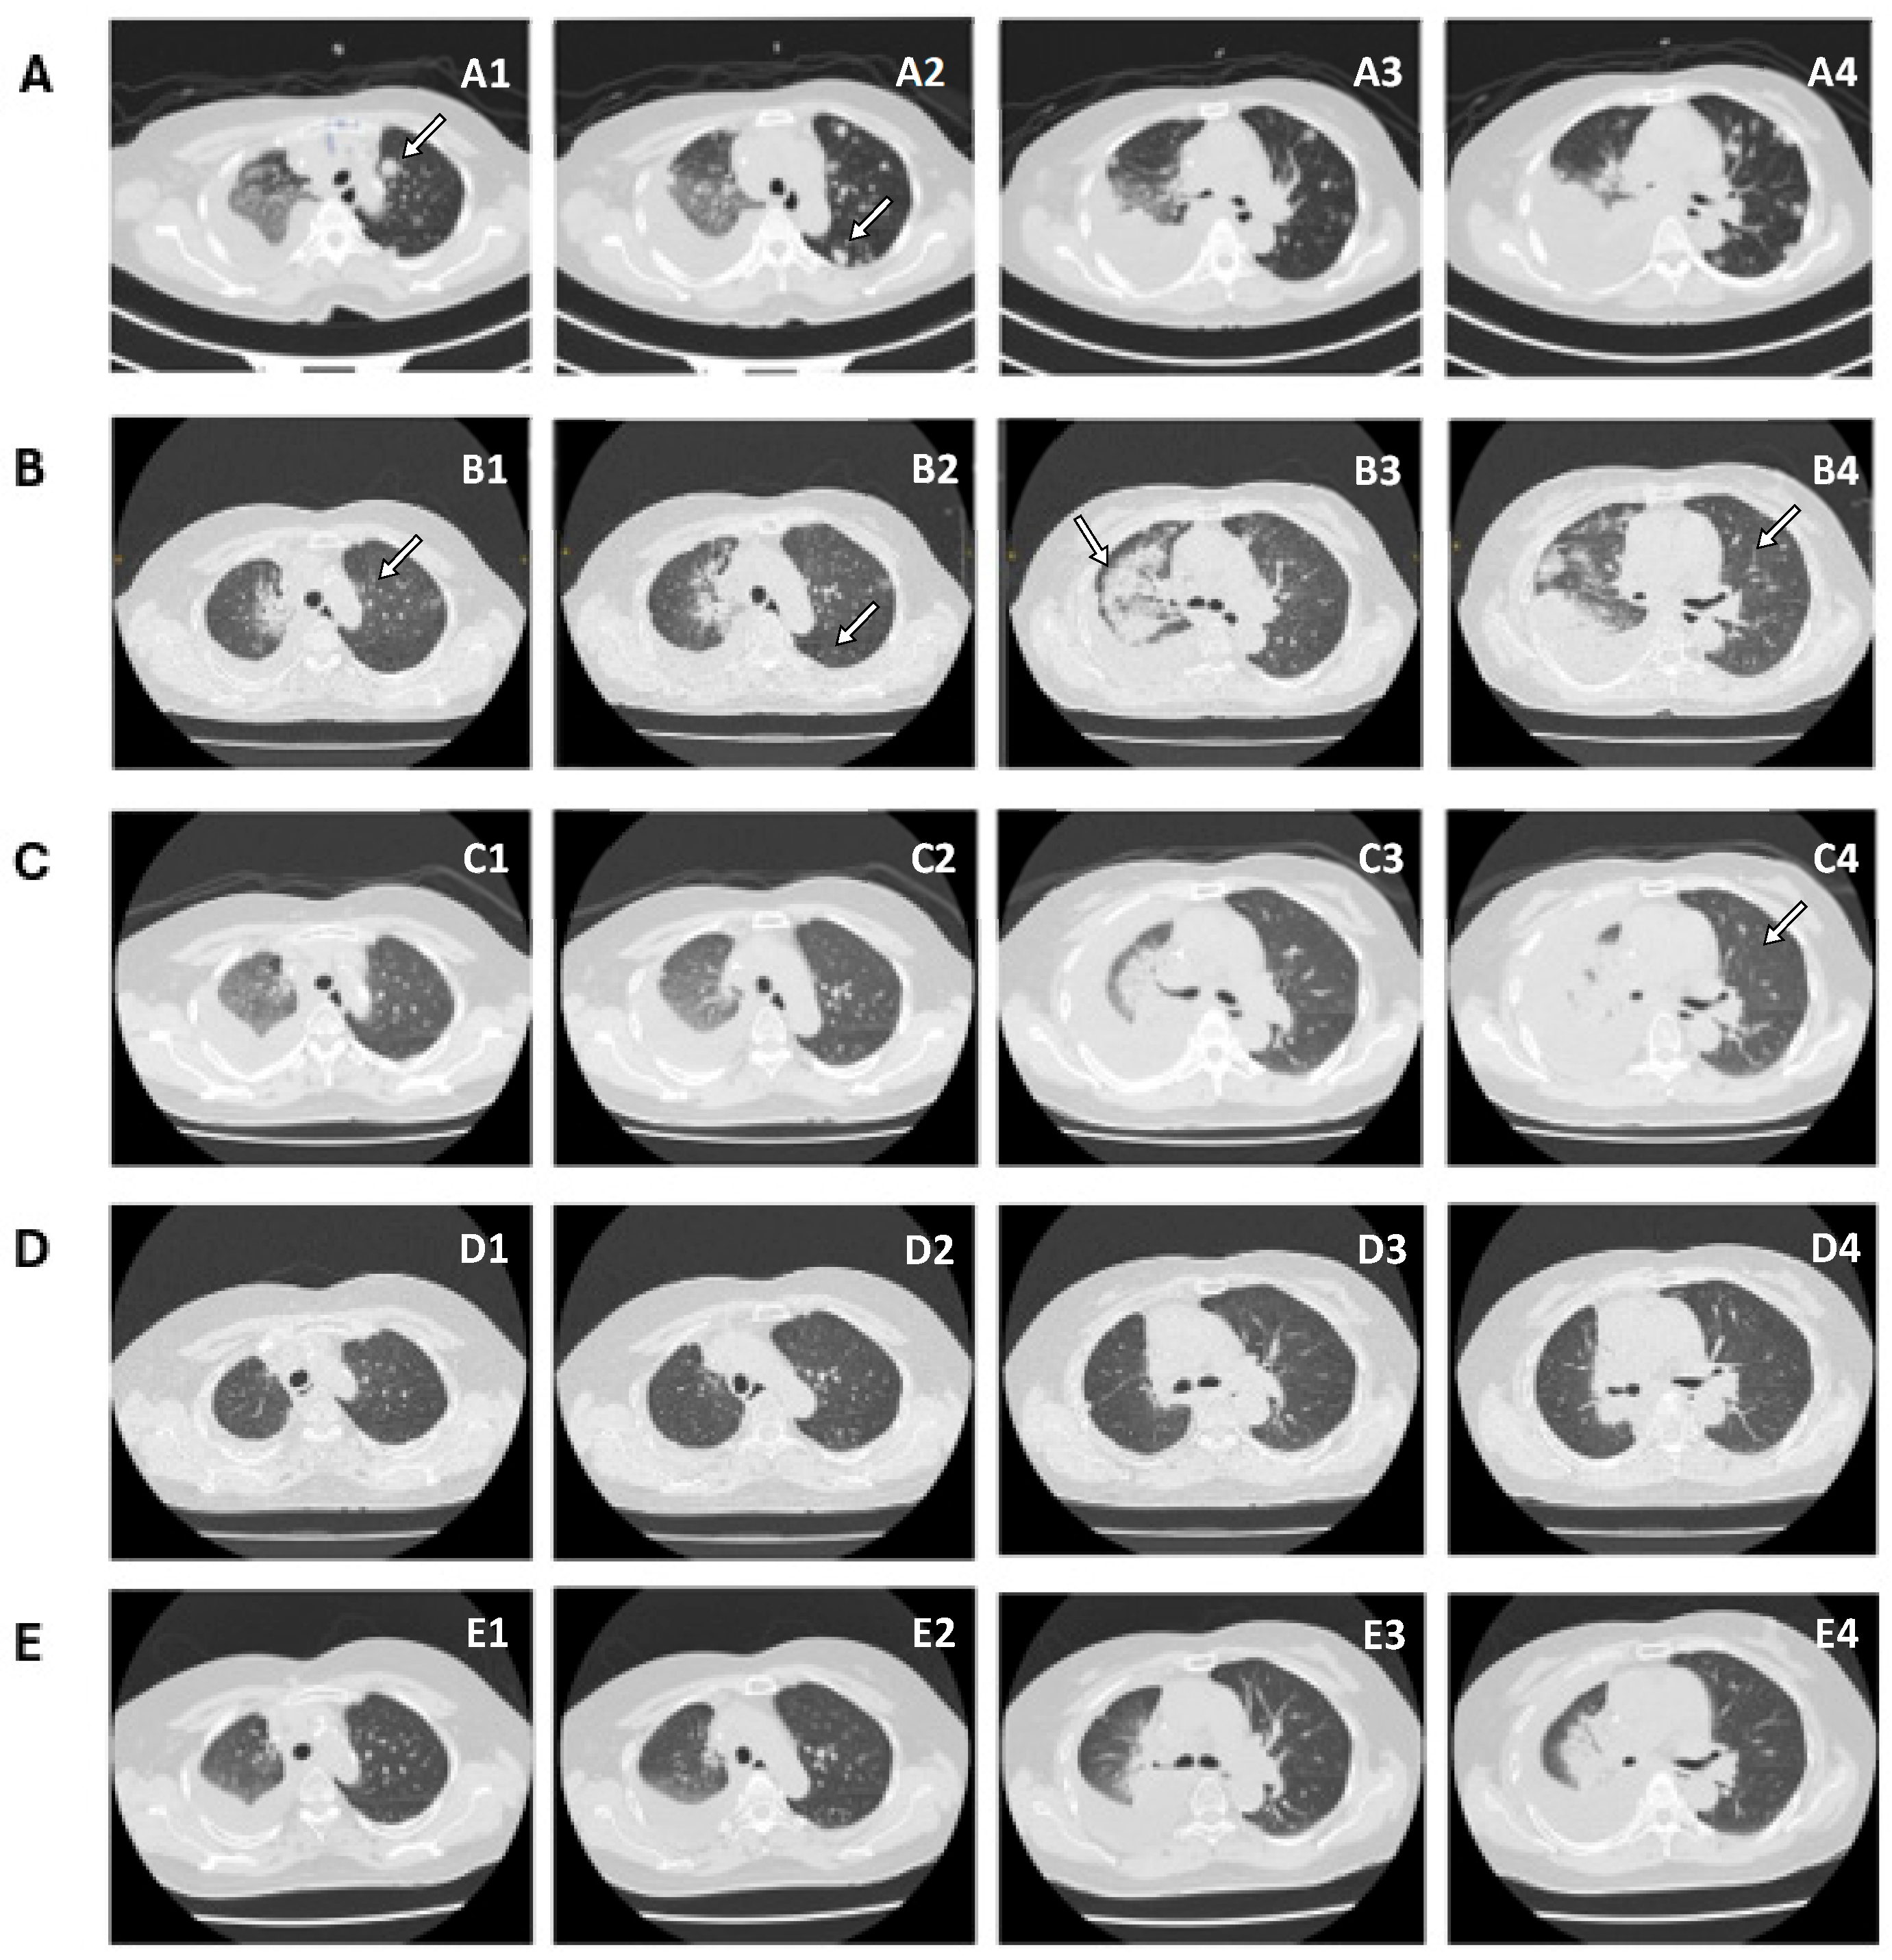

2. Case Presentation